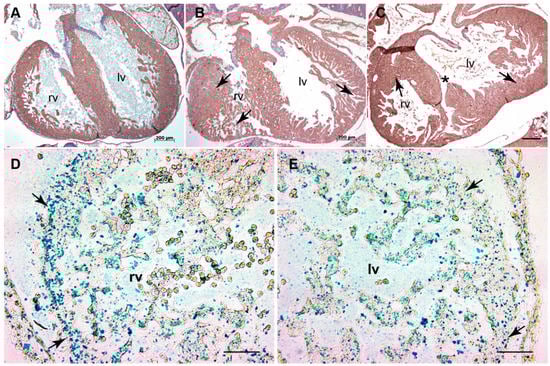

3.4. TGFβ3 Is Required for Extracellular Matrix Reorganization

3.5. Tgfb3 Deletion Leads to Hyper-Activated SMAD2/3 and SMAD1/5 Signaling Pathways